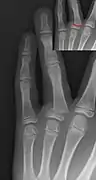

Salter–Harris II fracture of ring finger proximal phalanx.

Salter–Harris III fracture of big toe proximal phalanx.